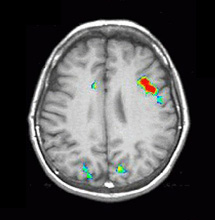

| Activation |

Broca's area and left SMA are depicted. Some activation appears in the left hippocampal formation and visual areas. This last activation could be explained as the effect of picturing the objects given during the "ON" condition. There is also activation in the right cerebellum and left inferior temporal gyrus.